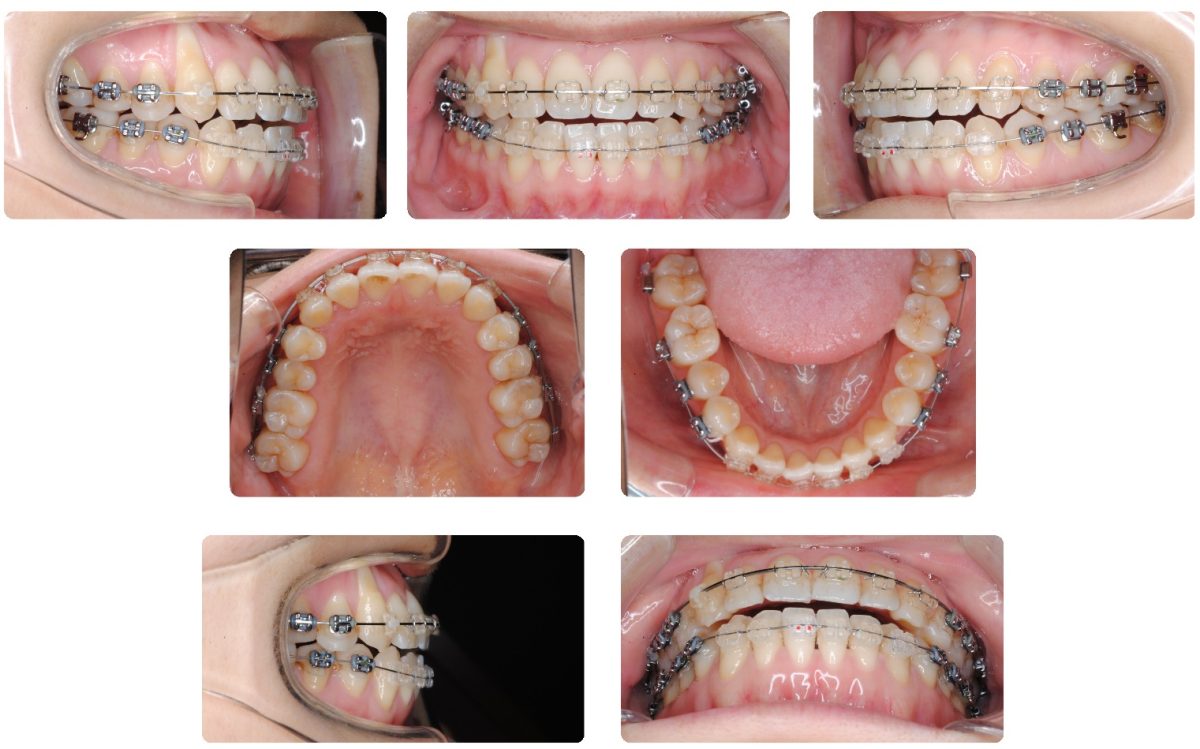

装置名:マルチブラケット装置

上顎歯列拡大を別途行ったのちに上下あごにマルチブラケット装置により個々の歯を並べました。